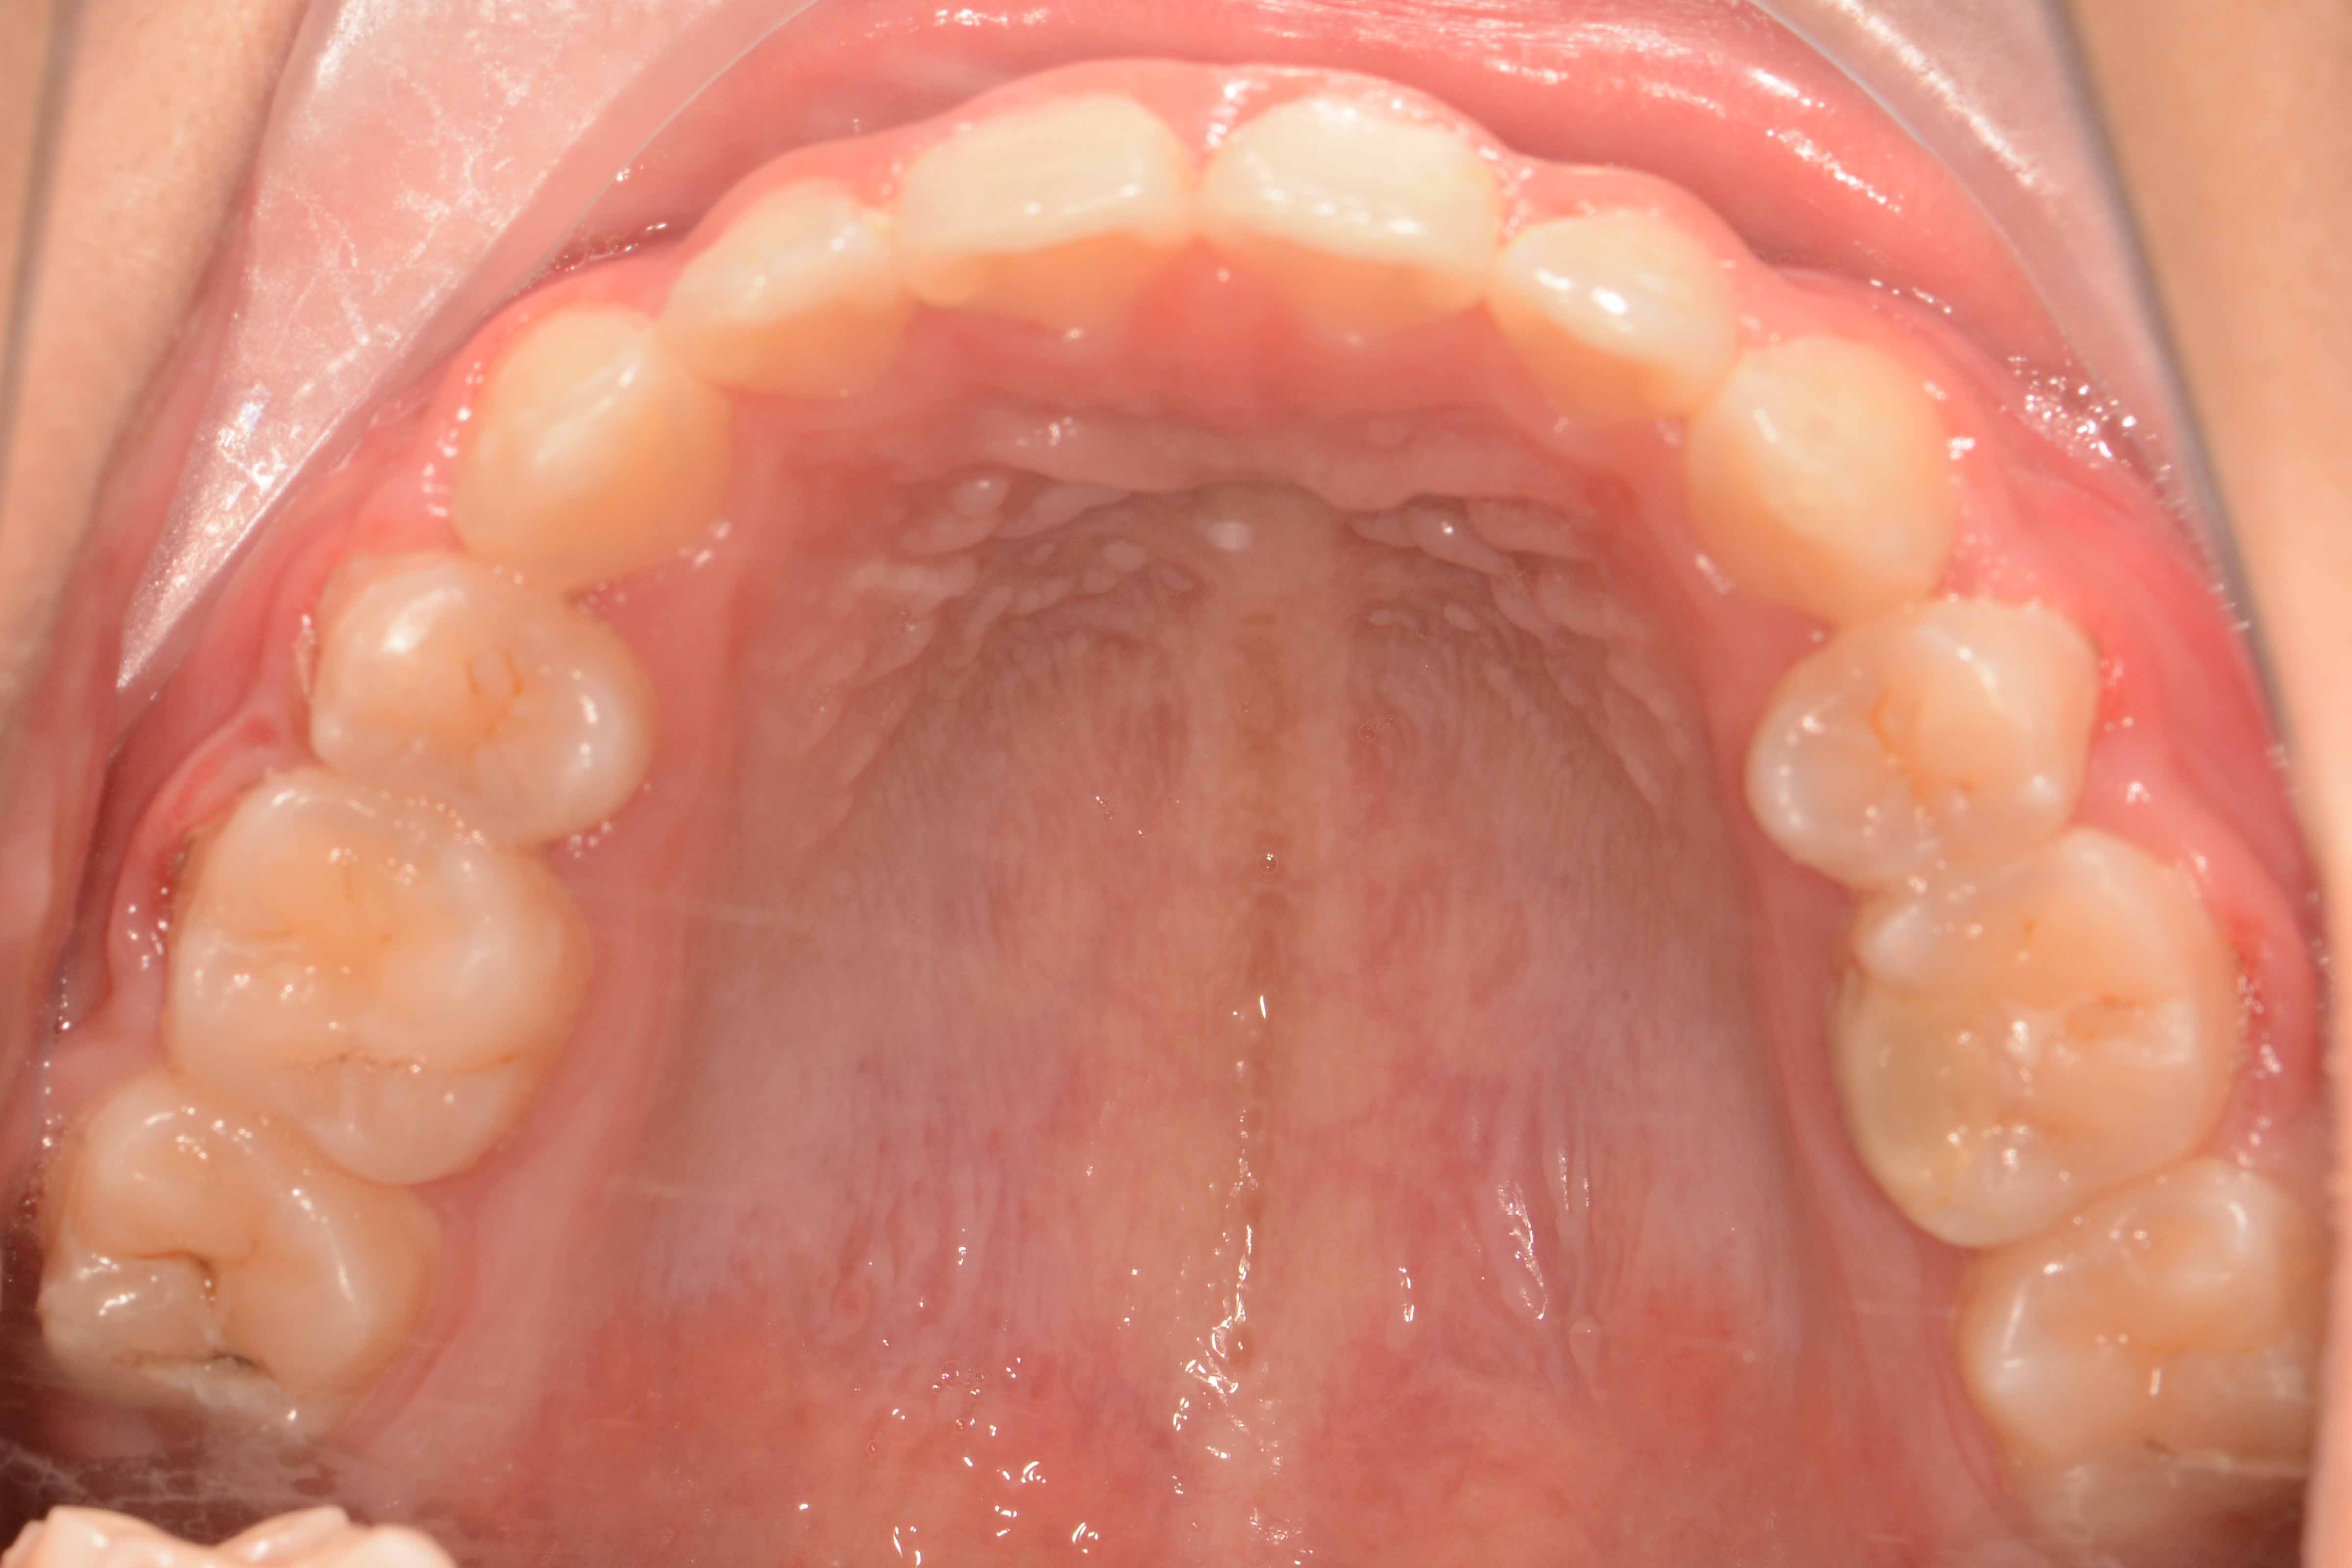

患者:14岁女性

诊断:安氏II类错颌畸形  开颌

治疗方案:拔除14 24 35 45,排齐整平牙列,调整覆合覆盖至正常,关闭间隙,精调,保持。

矫治前: